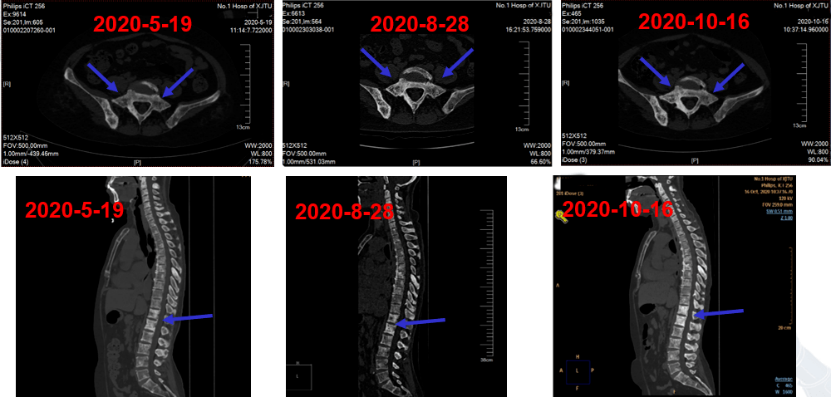

患者于2020年8月起更换为地舒单抗(120mg,q4w)治疗骨转移病灶, 下颌骨部疼痛明显缓解。2020年10月16日复查胸腰椎及肋骨三维重建提示:与前片相比, 原多发溶骨性转移灶钙盐沉积,骨密度增加,出现成骨性改变(图18)。

图18:地舒单抗治疗后,骨CT显示钙盐沉积,成骨性改变,骨密度增加

患者确诊骨转移后即开始双膦酸盐治疗,先后使用唑来膦酸及伊班膦酸钠,但骨病灶仍进展,并出现明显下颌骨疼痛,NRS评分显著升高。随后更换为地舒单抗治疗,疼痛明显缓解。影像学随访提示原多发溶骨性病灶出现钙盐沉积及骨密度增加,呈成骨性改变;碱性磷酸酶水平及NRS评分稳定下降,肌酐及血清钙始终维持在正常范围。